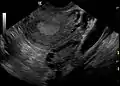

| A polycystic ovary shown on an ultrasound image. | |

The syndrome acquired its most widely used name due to the common sign on ultrasound examination of multiple (poly) ovarian cysts. These "cysts" are actually immature follicles not cysts. The follicles have developed from primordial follicles, but the development has stopped ("arrested") at an early antral stage due to the disturbed ovarian function. The follicles may be oriented along the ovarian periphery, appearing as a 'string of pearls' on ultrasound examination.

Not everyone with PCOS has polycystic ovaries (PCO), nor does everyone with ovarian cysts have PCOS; although a pelvic ultrasound is a major diagnostic tool, it is not the only one.[58] The diagnosis is straightforward using the Rotterdam criteria, even when the syndrome is associated with a wide range of symptoms.

- Gynecologic ultrasonography, specifically looking for small ovarian follicles. These are believed to be the result of disturbed ovarian function with failed ovulation, reflected by the infrequent or absent menstruation that is typical of the condition. In a normal menstrual cycle, one egg is released from a dominant follicle – in essence, a cyst that bursts to release the egg. After ovulation, the follicle remnant is transformed into a progesterone-producing corpus luteum, which shrinks and disappears after approximately 12–14 days. In PCOS, there is a so-called "follicular arrest"; i.e., several follicles develop to a size of 5–7 mm, but not further. No single follicle reaches the preovulatory size (16 mm or more). According to the Rotterdam criteria, which are widely used for diagnosis,[10] 12 or more small follicles should be seen in an ovary on ultrasound examination.[59] More recent research suggests that there should be at least 25 follicles in an ovary to designate it as having polycystic ovarian morphology (PCOM) in women aged 18–35 years.[65] The follicles may be oriented in the periphery, giving the appearance of a 'string of pearls'.[66] If a high resolution transvaginal ultrasonography machine is not available, an ovarian volume of at least 10 ml is regarded as an acceptable definition of having polycystic ovarian morphology instead of follicle count.[65]

Ultrasound findings in PCOS include enlarged ovaries with peripheral follicles in a "string of pearls" configuration.